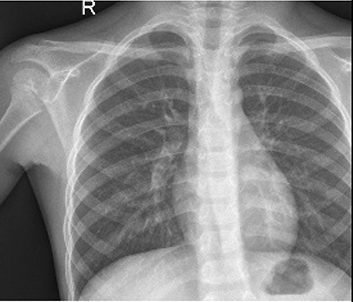

Table 6 Fused image output.

From: Multimodal medical image fusion combining saliency perception and generative adversarial network